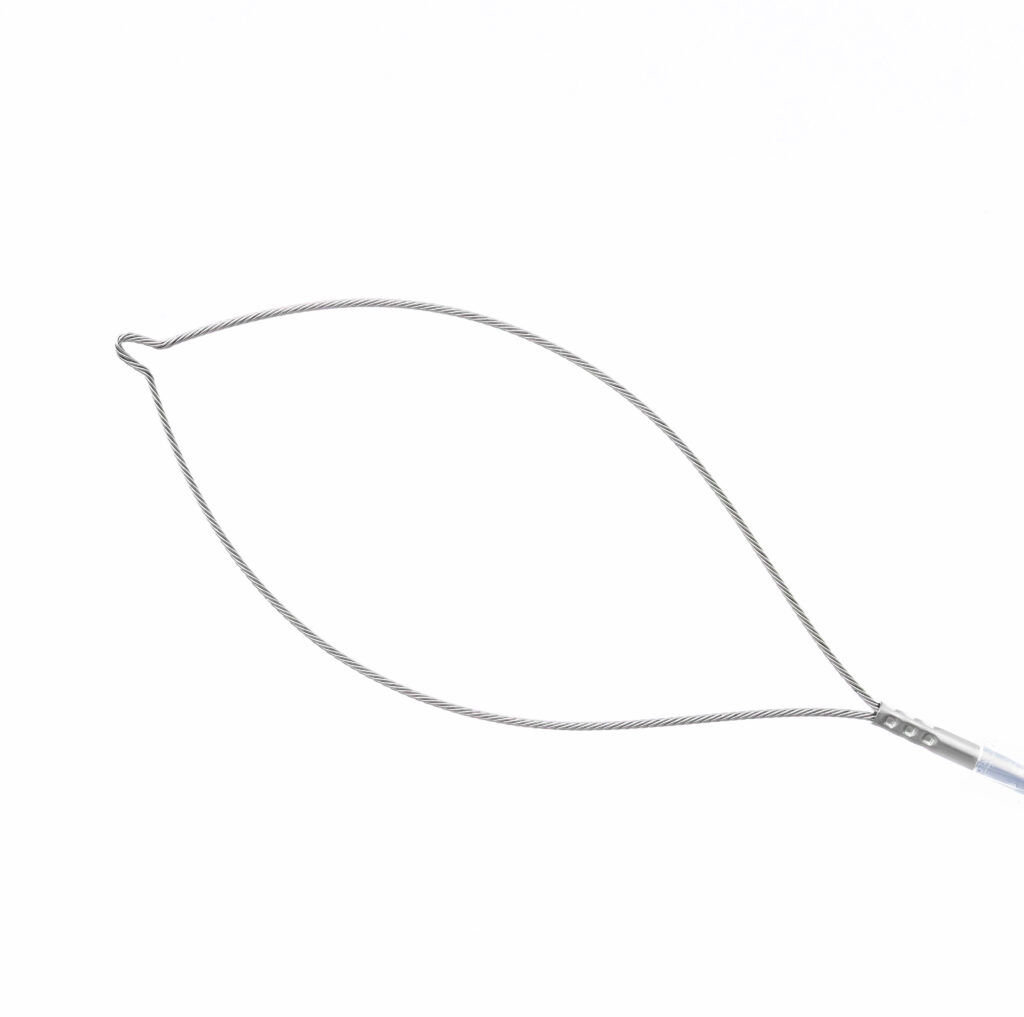

To make the removal of polyps in everyday routine as efficient as possible, Micro-Tech has developed a range of disposable polypectomy snares which perfectly combine quality with cost effectiveness. Each oval snare is made of a specially stranded wire, with enduring radial force, high dimensional stability, and precise cutting properties. The 3-ring handle offers a secure hold and transmits every movement reliably to the snare.

- High strength of shape